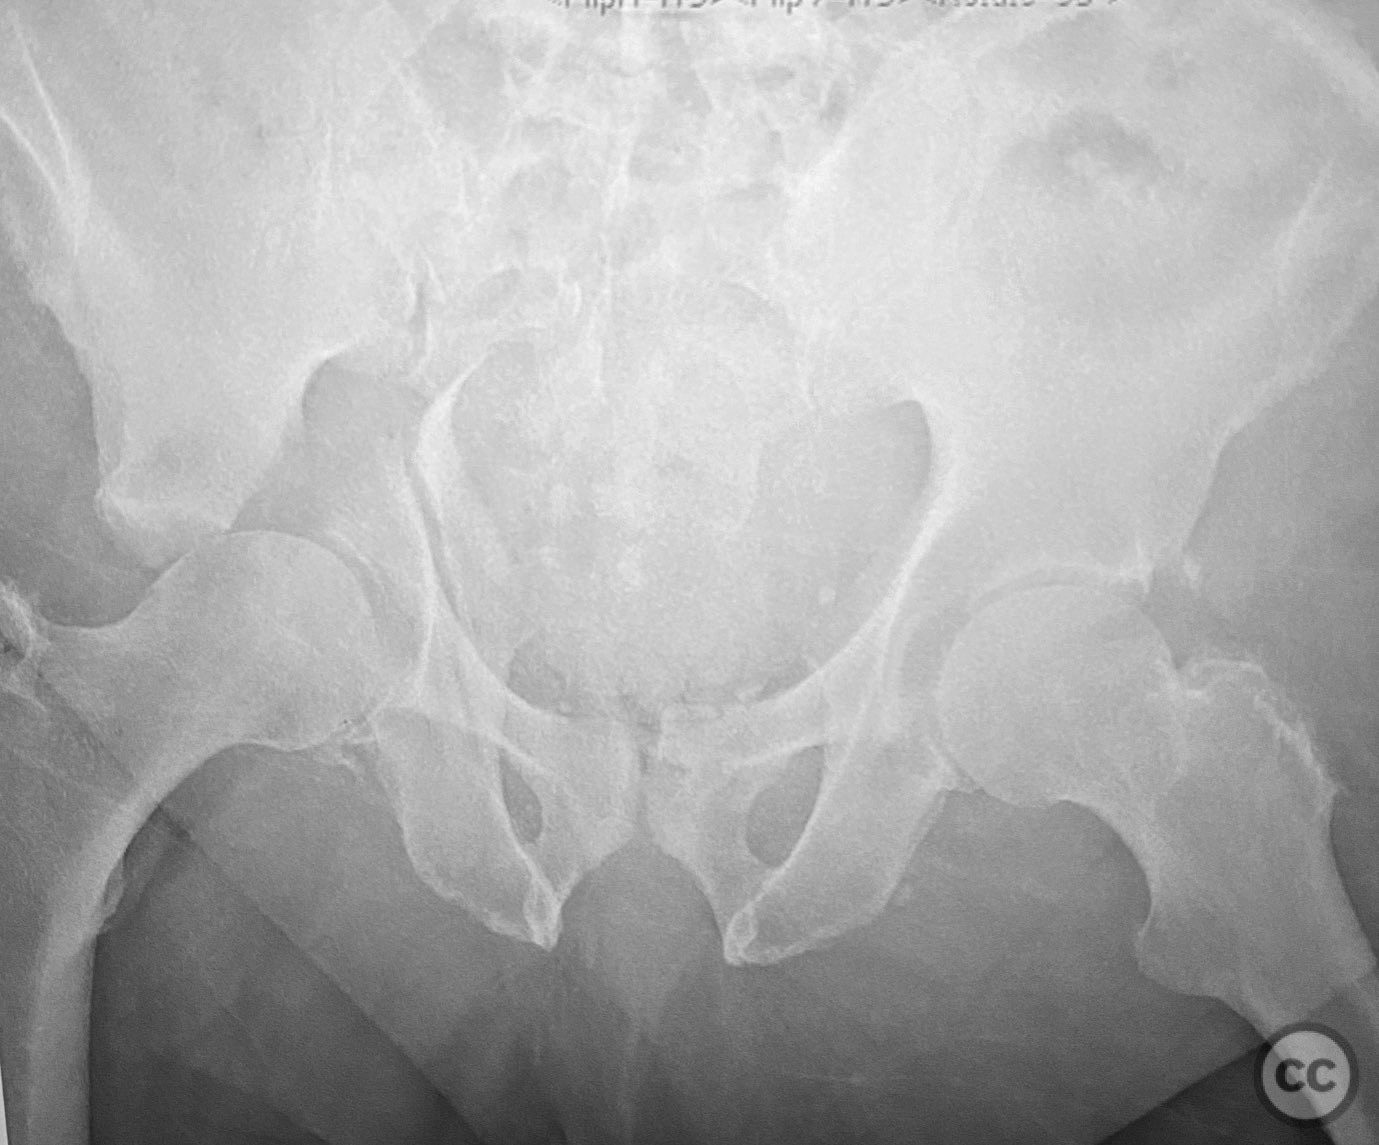

Clinical Details

Clinical and radiological findings:  A 79-year-old male sustained a high-energy injury in a motor vehicle collision, resulting in a complex acetabular fracture-dislocation. Radiographs and computed tomography demonstrated a posterior wall and transverse acetabular fracture (AO/OTA 62-B1.3), with the posterior wall fragments displaying an atypical caudal hinge configuration. The medial wall fragment was non-articular. Axial imaging revealed an impacted osteochondral fragment obstructing reduction, as well as disruption of the capsular structures adjacent to the intact articular segment. The obturator internus tendon appeared taut but intact, with no evidence of sciatic nerve impingement or superior gluteal neurovascular compromise.